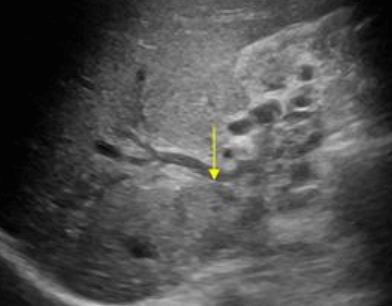

US finding

- 담낭관 또는 담낭 경부에 결석이 확인된다.

- 총간관(CHD) 또는 담낭관(cystic duct)의 확장소견이 보인다.

- 간내외 담관의 확장이 관찰된다.